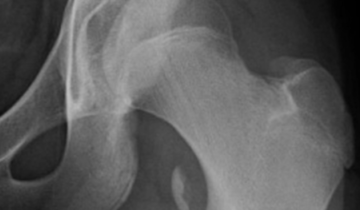

The Extremities

Differential Diagnosis